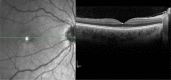

Ocular side effects of biological agents in oncology: what should the clinician be aware of?

During the last 20 years, biologicals have become increasingly relevant in oncologic therapy. Depending on the medication used, there are different profiles of ocular side effects. Although these can be present in up to 70% of patients, they are generally underreported in the literature. Therefore, the pathophysiological details of their development are often poorly understood. Herein we attempt to identify groups of biologicals to which a specific side effect profile can be assigned. We also tried to capture all relevant side effects and therefore conducted several database investigation including Medline, Cochrane library, and the drugs section of the US Food and Drug Administration (FDA), using the following search strings: "name of biological agent (both generic and commercial names)" AND "eye" OR "ocular". If we found a side effect that has been associated with a drug, we researched Medline using the following search string: "name of biological agent" (both generic and commercial names) AND "term for the specific side effect". Due to the wealth of material we report only the drugs that are approved by the FDA.